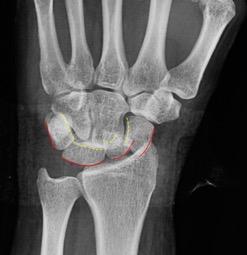

Perilunär luxation innebär en luxation mellan karpalben och lunatum. Missad skada slutar ofta med total handledsartrodes. För att upptäcka skadan på röntgen bör man leta efter oordning bland karpalbenen och avbrott i Gi lulas linjer som i normalfallet förlöper som två harmoniska bågar (se bild). Skadan framträder oftast tydligast på sidobilden med capitatums läge dorsalt beläget om lunatum. Obser vera medianusfunktionen och gör ett försök till sluten reposition. Patient en ska behandlas på operation med stiftning och ligamentsutur oavsett om repositionen lyckats eller ej.

Arvid von Konow Gilulas linjer ska löpa som två harmoniska bågar i carpallederna. Perilunär luxation ses oftast tydligast på sidobilden. Vid skada blir bågarna störda och svåra att följa. Vid Seymourfraktur genom fysen på distala falangen blir ofta nagelbädden nedslagen i frakturen.Läkning efter hälseneruptur sker i tre faser: